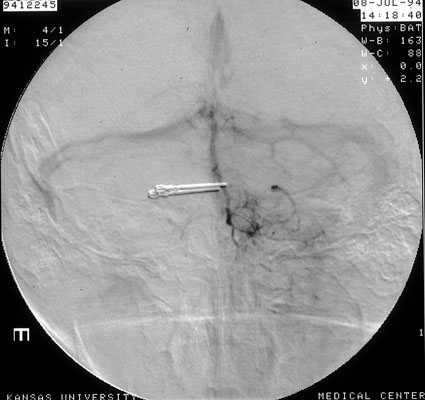

Arteriogram, berry aneurysm, post surgery

Same patient: postoperative arteriogram shows metal clamp applied during surgery, but aneurysm is no longer visible (this is digital subtraction angiography, which give a 3D effect. Everything is digitally subtracted from the image except the vessels of interest).